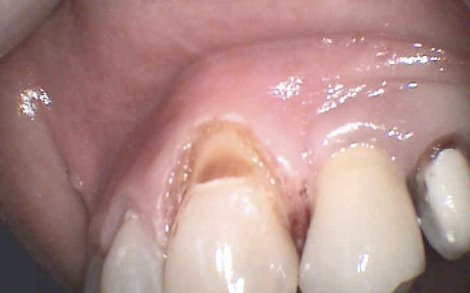

Paola e i colletti ipersensibili

dente malandatodi Michele Bonfrate * Domanda Paola sul gruppo Facebook: io ho due colletti dentali ipersensibili al freddo, non e’ che invece di andare dal dentista può intervenire la Tev…..

Le lesioni non-cariose del colletto sono difetti del dente interessanti sia i denti anteriori sia i posteriori; sono localizzate nella zona di confine tra corona e radice comunemente chiamata colletto del dente.

Queste lesioni sono il risultato di una perdita di struttura dentale (smalto e soprattutto dentina) derivante da erosione chimica,abrasione, stress masticatori o una combinazione di tali fattori.

colletto

Quali sono le cause responsabili della loro formazione?

• L’erosione del dente è correlata al frequente consumo di cibi acidi o bevande, ma anche al reflusso gastrico o rigurgito. La presenza cronica di sostanze acide nella bocca causa una lenta dissoluzione della sostanza minerale del dente, contribuendo alla formazione dei difetti del colletto.

• L’abrasione del dente è invece correlata all’uso di dentifrici abrasivi e ad un’incorretta tecnica di spazzolamento. Il risultato finale è l’usura meccanica del colletto del dente, dove lo spessore di smalto è più sottile.

• Gli stress masticatori causano una flessione del dente nella zona del colletto. Questi ripetuti insulti sono responsabili dell’insorgenza di micro-fratture che tendono a convergere fino a formare, nel tempo, vere e proprie lesioni del colletto. Pazienti che digrignano i denti, pazienti con denti mancanti o ruotati sono particolarmente suscettibili alla formazione di questi difetti.

Devono essere curate?

Le lesioni non-cariose del colletto comportano l’esposizione della dentina (la dentina contiene le terminazioni nervose) e possono comportare l’insorgenza di una spiccata sensibilità; questa, talvolta, si può trasformare in vera e propria nevralgia sotto particolari stimoli (caldo o freddo). Inoltre, i difetti del colletto possono indebolire la struttura del dente ed essere anti-estetici.

Per tutte queste ragioni, le lesioni del colletto devono essere trattate anche in assenza di carie.

In primo luogo, si devono eliminare le cause che hanno determinato l’insorgenza delle lesioni; in seguito, si deve procedere all’otturazione del difetto utilizzando materiali da otturazioni bianchi in resina composita.